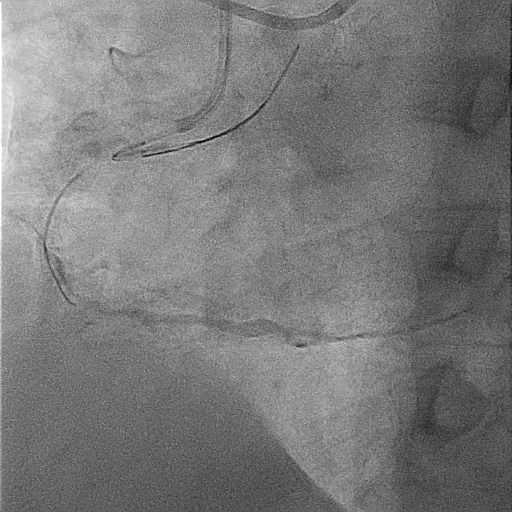

A 51-year-old man presented with stable angina and previously failed right coronary artery (RCA) CTO PCI. During RCA CTO PCI (Figure 1), the wire was inserted into the extraplaque space (Figure 2, Video 1). Intravascular ultrasound (IVUS) showed a hematoma (Figure 3A, Video 2). Live 3-dimensional tip detection IVUS wiring was successful (Figure 4, Video 3). A FineCross microcatheter (Terumo) was placed over the first wire into the extraplaque space and blood was withdrawn by connecting a negative indeflator to the microcatheter. Stents were deployed (Figure 5) and postdilated. Post-IVUS showed almost complete resolution of the hematoma (Figure 3B, C; Video 4) with good results (Figure 6, Video 5).